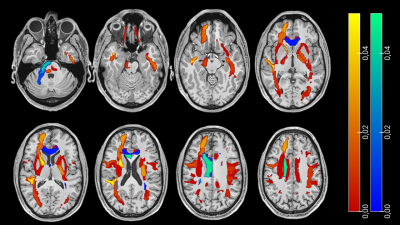

Diffusion MRI tractography is a non-invasive neuroimaging technique used to study the brain's white matter connections. In epilepsy, it has for example been used to identify and visualize abnormal white matter tracts and to plan surgical interventions. This talk will highlight methodological aspects of the technique, applications, and potential pitfalls related to its reliability and validity for use in clinical practice.

This talk examines current diffusion MRI modeling approaches for brain tissue. Biophysical models and signal representations are contrasted. How diffusion coarse-graining facilitates modeling is explained. Emphasis is put on the identification of common modeling assumptions and examples on how to validate them. High diffusion weightings, long and short diffusion times, and variable tensor encodings are discussed together with state-of-the-art modeling techniques on each. Finally, present and future directions for modeling white and gray matter are discussed.

Validations in phantoms, preclinical, and histological studies have greatly enhanced our understanding of what in vivo diffusion measures reflect. However, there remain complexities in human imaging that can confound interpretations and mean that phantom, animal, and histology studies do not always perfectly translate. Validation in clinical and population studies remains important to better inform interpretation of diffusion metrics in human studies. I will cover diffusion validation studies in clinical and population studies in living humans. In particular, studies relating various diffusion and other metrics to one another provide context for interpretation and help evaluate the specificity of various diffusion metrics.